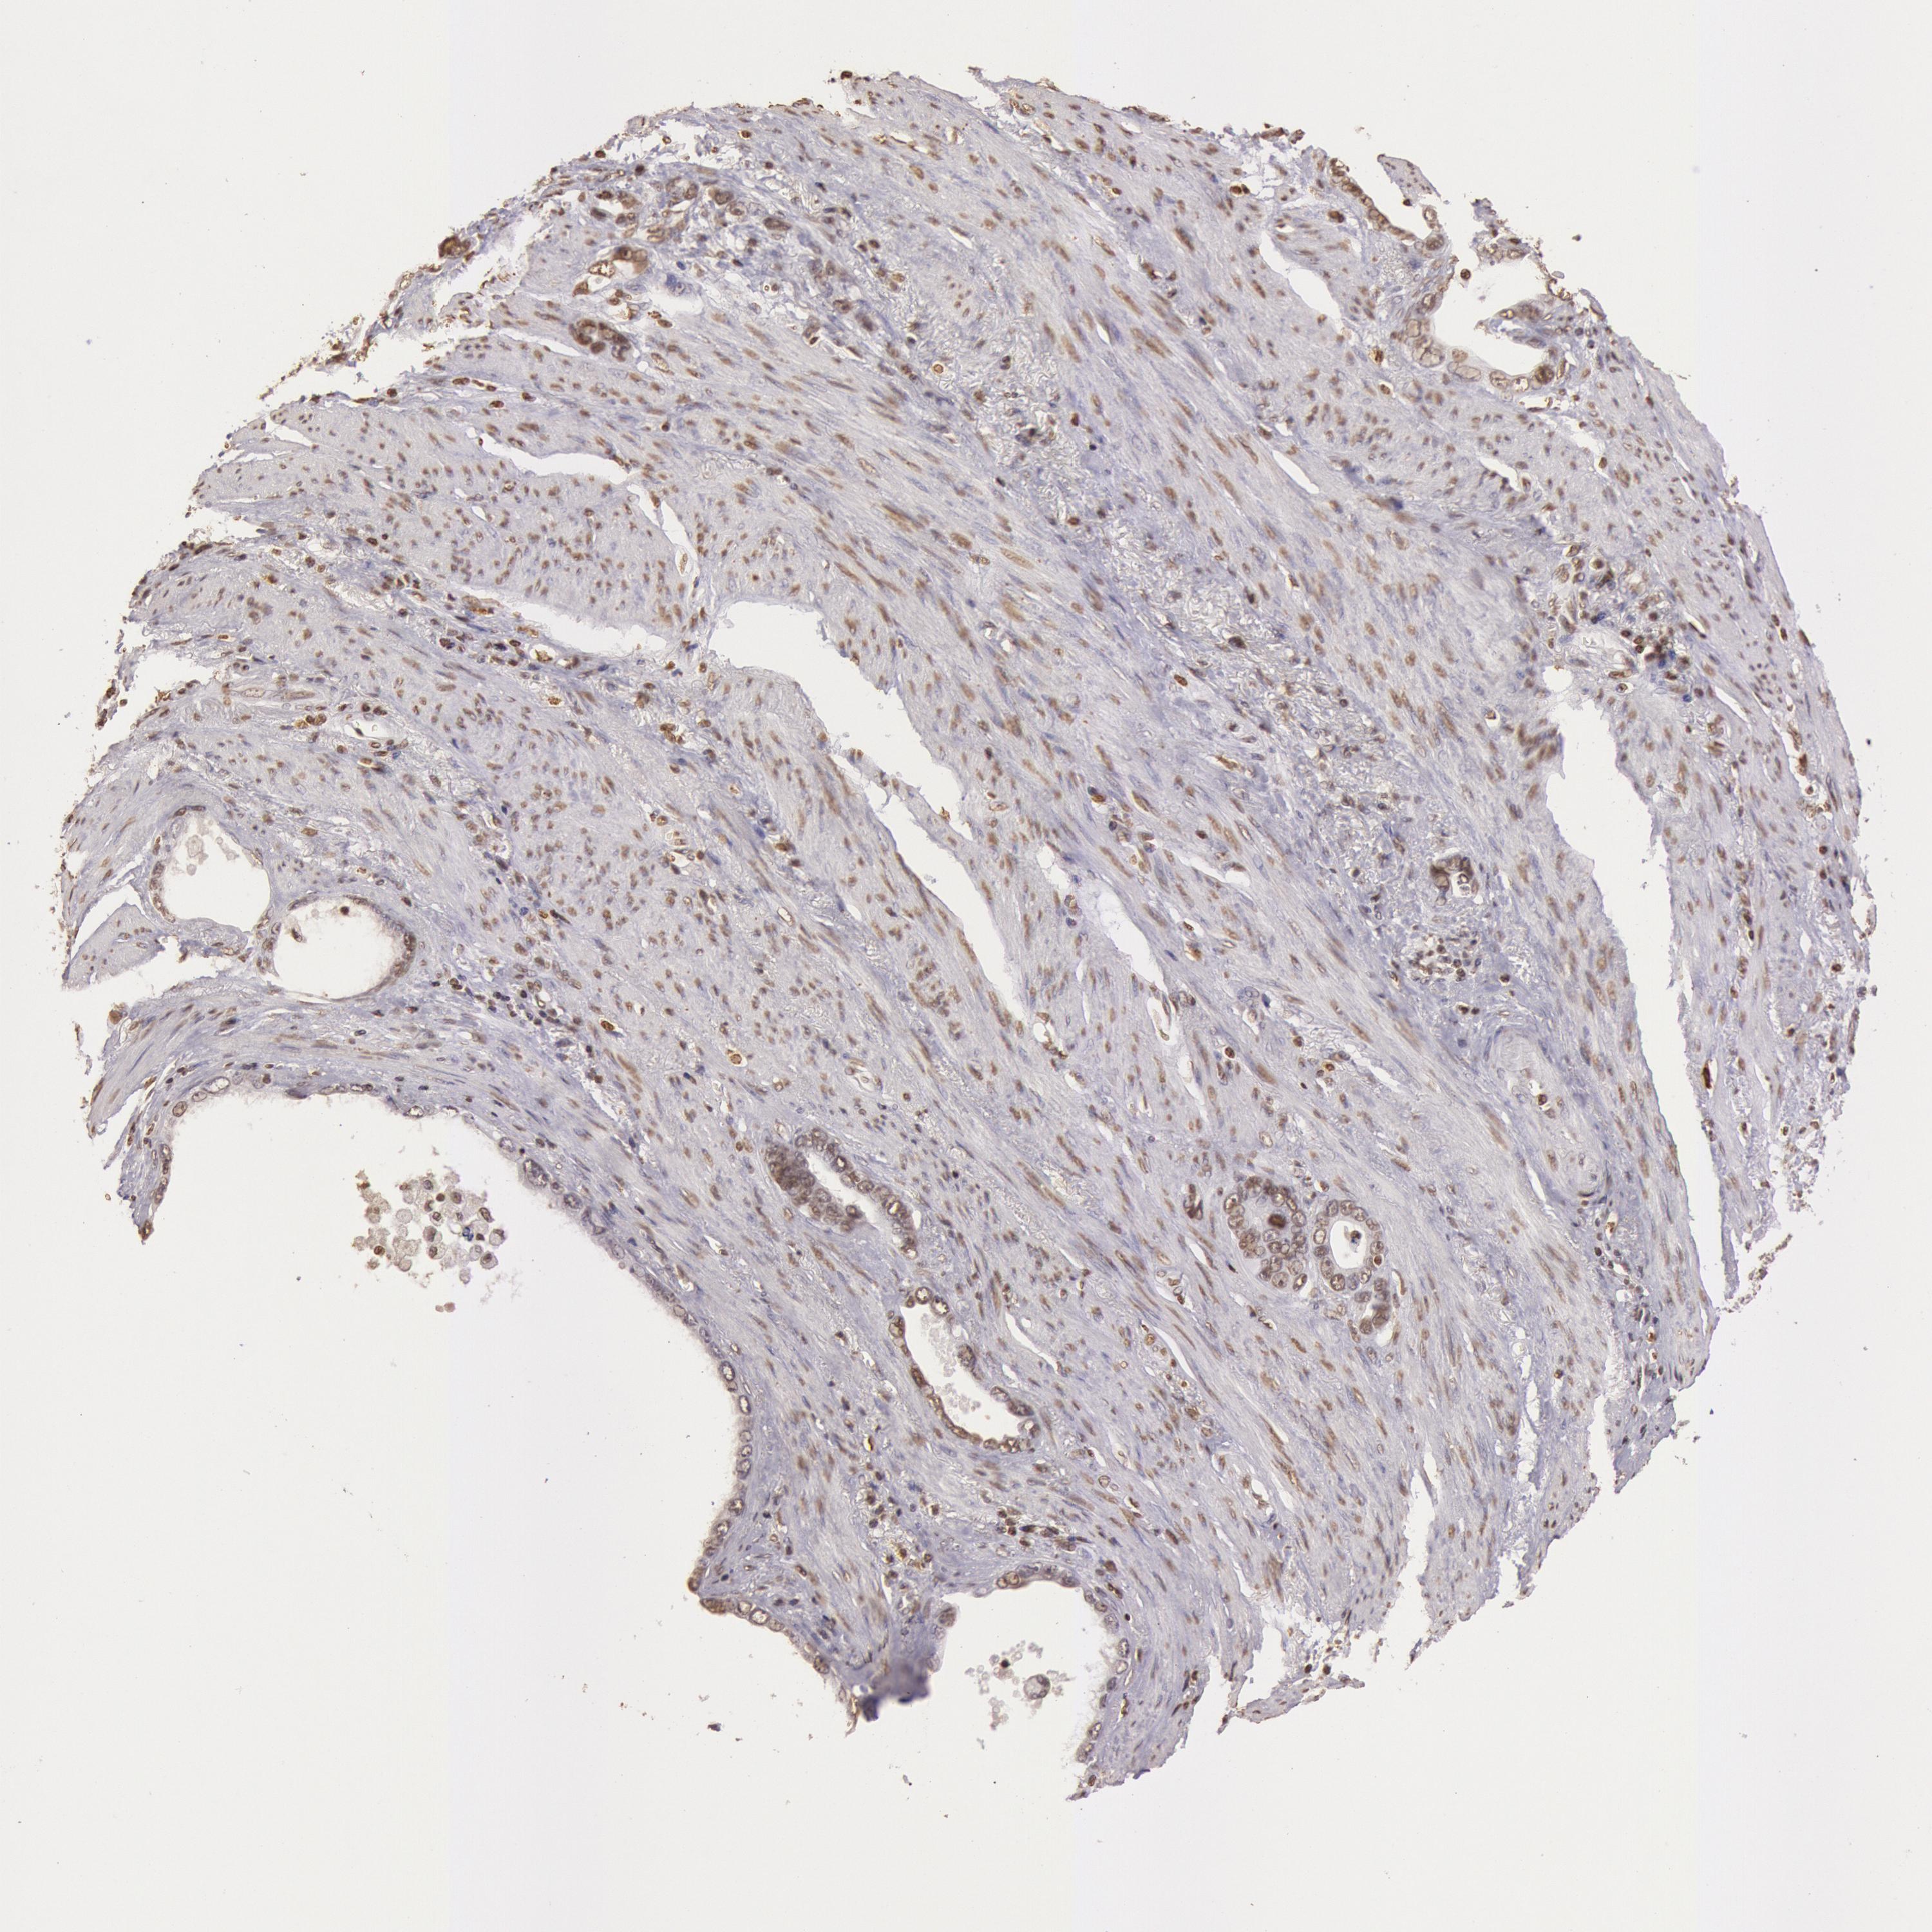

STOMACH CANCER - Protein expressioni

A mouse-over function shows sample information and annotation data. Click on an image to view it in a full screen mode. Samples can be filtered based on level of antibody staining by selecting one or several of the following categories: high, medium, low and not detected. The assay and annotation is described here.

Note that samples used for immunohistochemistry by the Human Protein Atlas do not correspond to samples in the TCGA dataset.

Antibody stainingi

Antibody staining in the annotated cell types in the current human tissue is reported as not detected, low, medium, or high, based on conventional immunohistochemistry profiling in selected tissues. This score is based on the combination of the staining intensity and fraction of stained cells.

Each image is clickable and will lead to virtual microscopy that enables deeper exploration of all samples and also displays staining intensity scores, fraction scores and subcellular localization as well as patient and tissue information for each sample.

Antibody HPA001401

Antibody CAB008670

Staining

High

Medium

Low

Not detected

Intensity

Strong

Moderate

Weak

Negative

Quantity

>75%

75%-25%

<25%

None

Location

Nuclear

Cytoplasmic/membranous

Cytoplasmic/membranous,nuclear

Adenocarcinoma, NOS